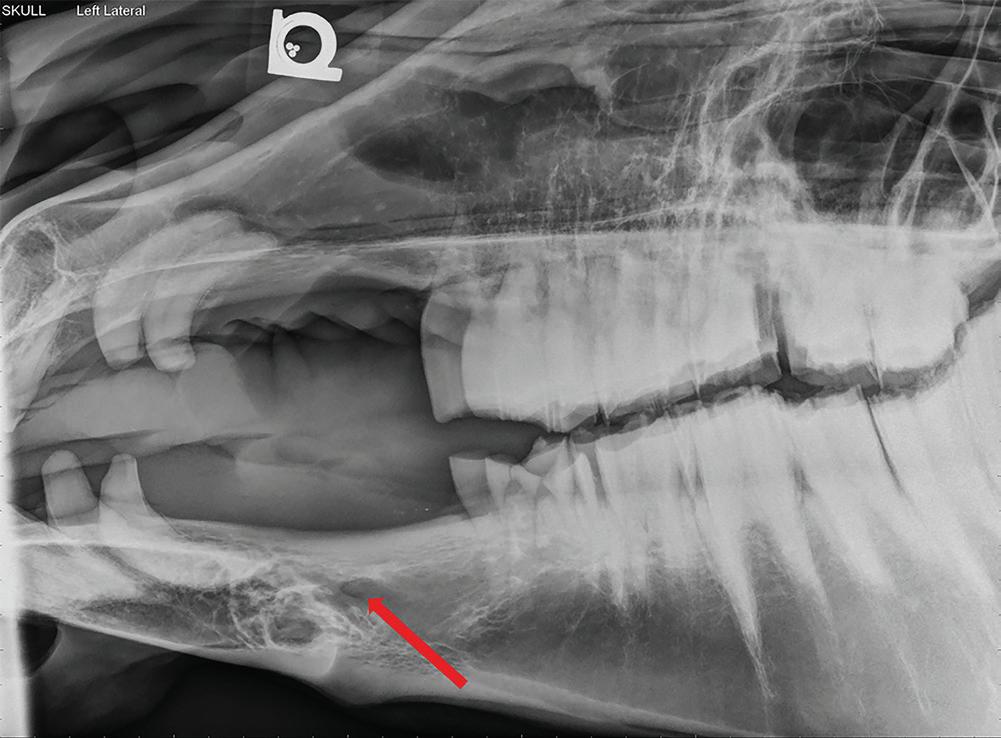

On endoscopy, narrowed nasal meati, purulent material, masses, or blood can be seen in

the nasal passage and/or draining from the sinus openings (Nickels 2012). Radiography of the skull may reveal free fluid lines, radiodense masses, paranasal sinus cysts, and lucency and/or proliferation associated with dental disease (Figure 1.1). Sinocentesis can be used to obtain fluid sample for culture and cytological examination. Sinuscopy with the horse standing and sedated is useful for the examination, diagnosis, and treatment of some disorders of the paranasal sinuses (Nickels 2012).

Figure 1.1 Lateral radiograph of a horse skull showing a fluid line (blue arrows) running through the caudal maxillary sinuses. The horse’s nose was angled downward resulting in the gravity-dependent fluid line being parallel to the ground. The sinusitis likely resulted from a periapical infection of a cheek tooth (red arrow). Maxillary nerve blockade can be used to desensitize the area for surgical removal of the tooth and drainage and lavage of the sinus.